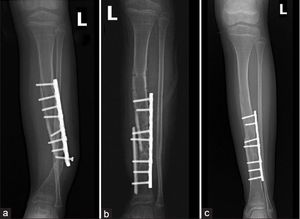

Medications IV bisphosphonates (pamidronate (Aredia®) and zoledronate (Reclast®/Zometa®) to increase bone mass; may be started in neonatal period if infant can breathe on own. Supplement with vitamin D and calcium as needed. Physical and occupational therapy beginning in infancy Both land and aquatic based programs. To improve function, address joint laxity, and improve cardiopulmonary status. To aid development of fine motor skills. To identify appropriate mobility aids. Surgery To correct bowing of long bones; may involve osteotomies. To insert rods (intramedullary rodding surgery) to support long bones. To stabilize the spine.